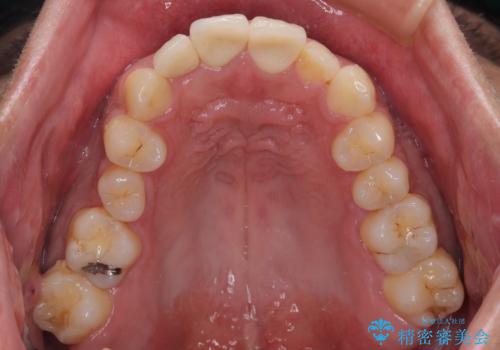

歯が欠けるほどの強い衝撃を受けると、歯根が溶けてしまう外部吸収という現象を起こすことがあるため、補綴治療後しばらく様子を見ておりましたが、何と三度自転車事故に遭いかけてしまいました。